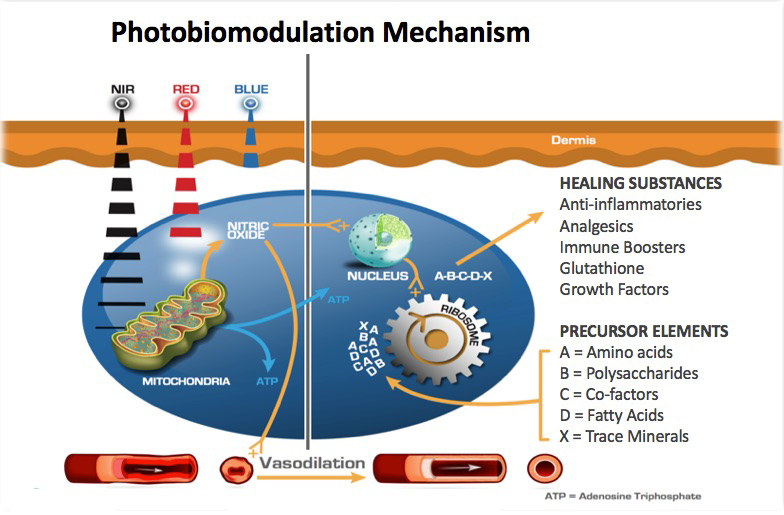

Uniquely, the proposed mechanism of PBM is the release of nitric oxide from cytochrome C-oxidase (COX) which increases ATP, genetic signalling to upregulate anti-inflammatory, local circulation, cell growth and protective factors. (7) (Fig 5) These processes promote improved brain function and subsequent clinical improvement. In a case series of 12 veterans with chronic mTBI lasting greater than 18 months, Hipskind et al demonstrated statistical improvements in cognitive function and rCBF using quantitative SPECT following PBMT. (Fig 7) This study used an FDA cleared InLight Medical PBM device (Fig 6) which pulsed both red (629nm) and near-infrared (850 nm) light transcranially for 20 minutes thrice per week for six weeks. Standard neuropsychological testing revealed improvements in 14 out of 15 subscales, with six of the 14 reaching statistical significance. In addition, quantitative brain SPECT imaging revealed improvements in rCBF in nine of 12 subjects. Subgroup statistical analysis of the nine with improved rCBF revealed quantitative blood flow improvements at the P<0.007 level. Although not formally evaluated, all subjects reported subjective improvements in mood, attention and sleep. There were no reported adverse effects.

Recently, modalities including neurofeedback, transcranial magnetic stimulation (TMS), hyperbaric oxygen therapy (HBOT) and photobiomodulation therapy (PBMT) have shown promise. However, only HBOT and PBMT have demonstrated the ability to actually upregulate and downregulate neuron genetic mechanisms. (13-15) These modalities appear to be equally effective in reversing the effects of mTBI on brain SPECT imaging. (13,15)